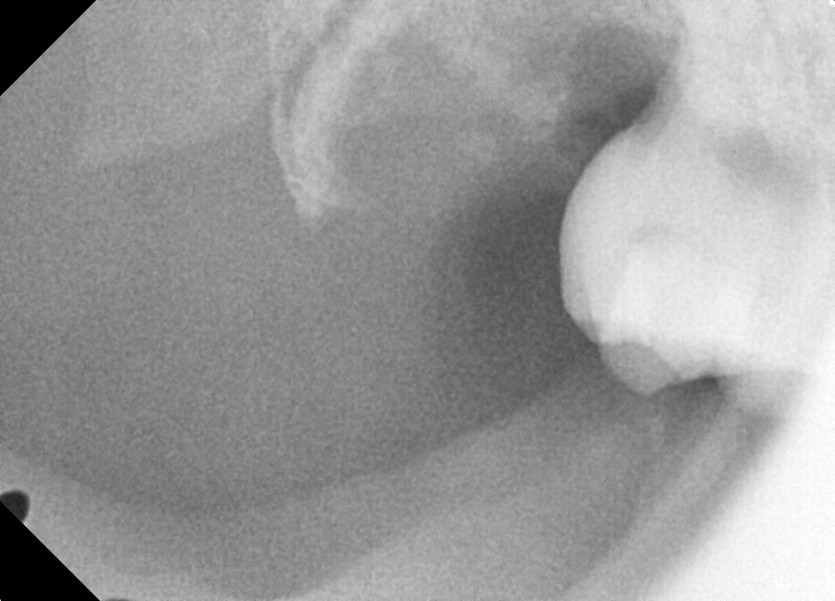

#18사랑니 발치 + #19 과잉치발치